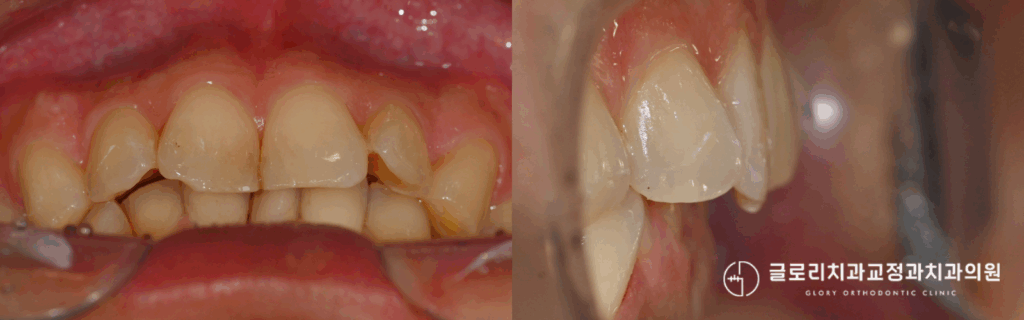

특히 윗니가 아랫니를 과하게 덮는 형태의 부정교합을 가진 분들은 웃을 때 잇몸이 많이 드러나거나, 아래 앞니가 거의 보이지 않아 고민이 깊어지기도 합니다.

과개교합이란 위아래 치아가 맞물릴 때 윗니가 아랫니를 지나치게 많이 덮고 있는 상태를 말합니다.

정상적인 교합에서는 윗니가 아랫니의 약 2~3mm 정도를 덮는 것이 이상적입니다.

그러나 과개교합인 경우, 아래 앞니가 거의 보이지 않을 정도로 윗니와 깊게 물리게 됩니다.

심한 경우에는 아래 앞니 끝이 위쪽 입천장 부근의 잇몸에 닿기도 합니다.

우선 아래 앞니가 위쪽 잇몸에 반복적으로 닿으면서 잇몸 손상이 발생합니다.

잇몸이 붓거나 염증이 생기는 경우도 있으며, 만성적인 자극으로 인해 잇몸 퇴축이 진행되기도 합니다.

또한 앞니에 과도한 힘이 집중되어 치아 마모가 빠르게 진행됩니다.

법랑질이 닳아 시린 증상이 나타나거나, 치아 끝부분이 불규칙하게 닳아 심미성이 저하되기도 합니다.